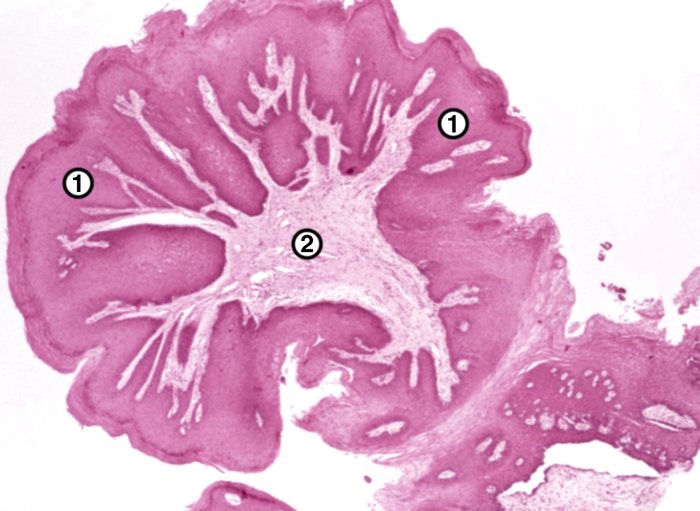

Микроскопически папиллома полости рта представляет собой опухоль, состоящую из высокодифференцированного многослойного плоского эпителия с признаками ороговения. Сохраняются целостность собственной мембраны, полярность клеток, комплексность. Нарушено соотношение структурных компонентов эпителия и стромы. Местами может наблюдаться очаговая воспалительная инфильтрация.

В отдельных случаях может фиксироваться очаговая воспалительная инфильтрация.

В ходе микроскопии выявляется увеличение числа капилляров в соединительной ткани. Митотическая активность возрастает, т. е. ускоряется деление клеток. Для выявления вируса папилломы 6 или 11 типа используется метод ПЦР (полимеразной цепной реакции).